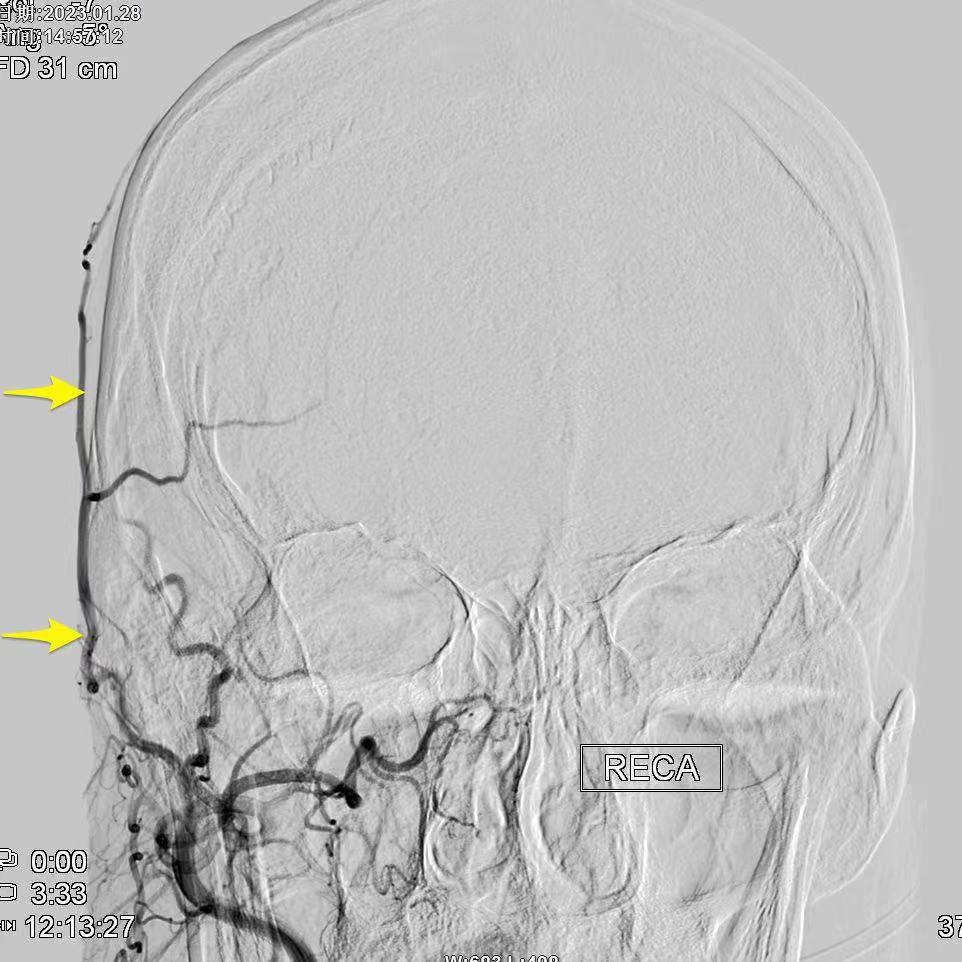

昆明三博2023:颞浅动脉一大脑中动脉M3吻合术